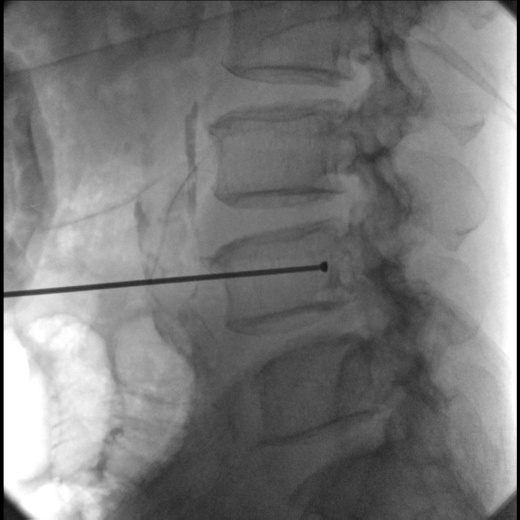

В качестве приемника используется динамический плоскопанельный детектор 26×26 см с разрешающей способностью более 4,5 пар.лин./мм., позволяющий визуализировать мельчайшие объекты с высоким разрешением. За счет применения динамического плоскопанельного детектора отсутствует эффект дисторсии, что повышает диагностическую значимость исследований. Большой диапазон выбора значений кадров с секунду при импульсной рентгеноскопии позволяет значительно снизить лучшею нагрузку, при этом при необходимости возможно проводить исследования с частотой до 30 кадров в секунду.

Автоматическая функция регулировки параметров рентгеноскопии с целью высокого проникновения при исследовании полных пациентов, а так же при сложных проекциях. - Качество снимков